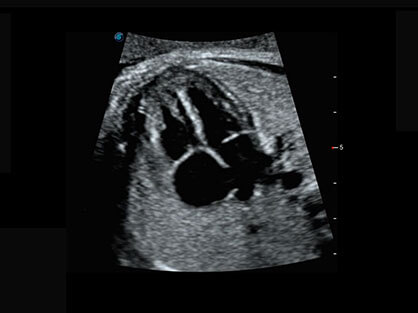

0.5mm厚度的薄层切片显像,可清晰显示微小病灶的连续断面。

可同时显示组织结构表面和内部的轮廓信息,达到透视效果,为临床提供更丰富的诊断信息。

卵泡结构的自动识别和测量,可显示多组测量数据。

大角度腔内容积探头,可完整包络子宫及盆底结构,充分展示组织结构毗邻关系。